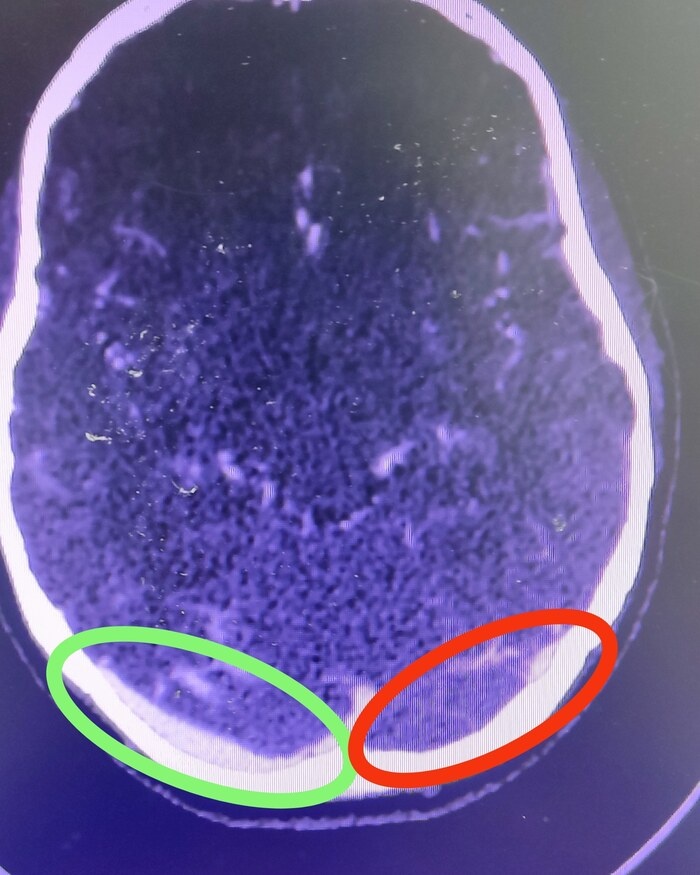

И прежде, чем проводить люмбальную пункцию с целью исследования спинномозговой жидкости, было решено провести компьютерно томографическую ангиографию сосудов головного мозга, где выявлен тромбоз поперечного синуса слева (на снимке он справа обведен красным цветом, потому что снимок отзеркален.)

Выставлен диагноз: Венозный инсульт на фоне тромбоза поперечного синуса слева.